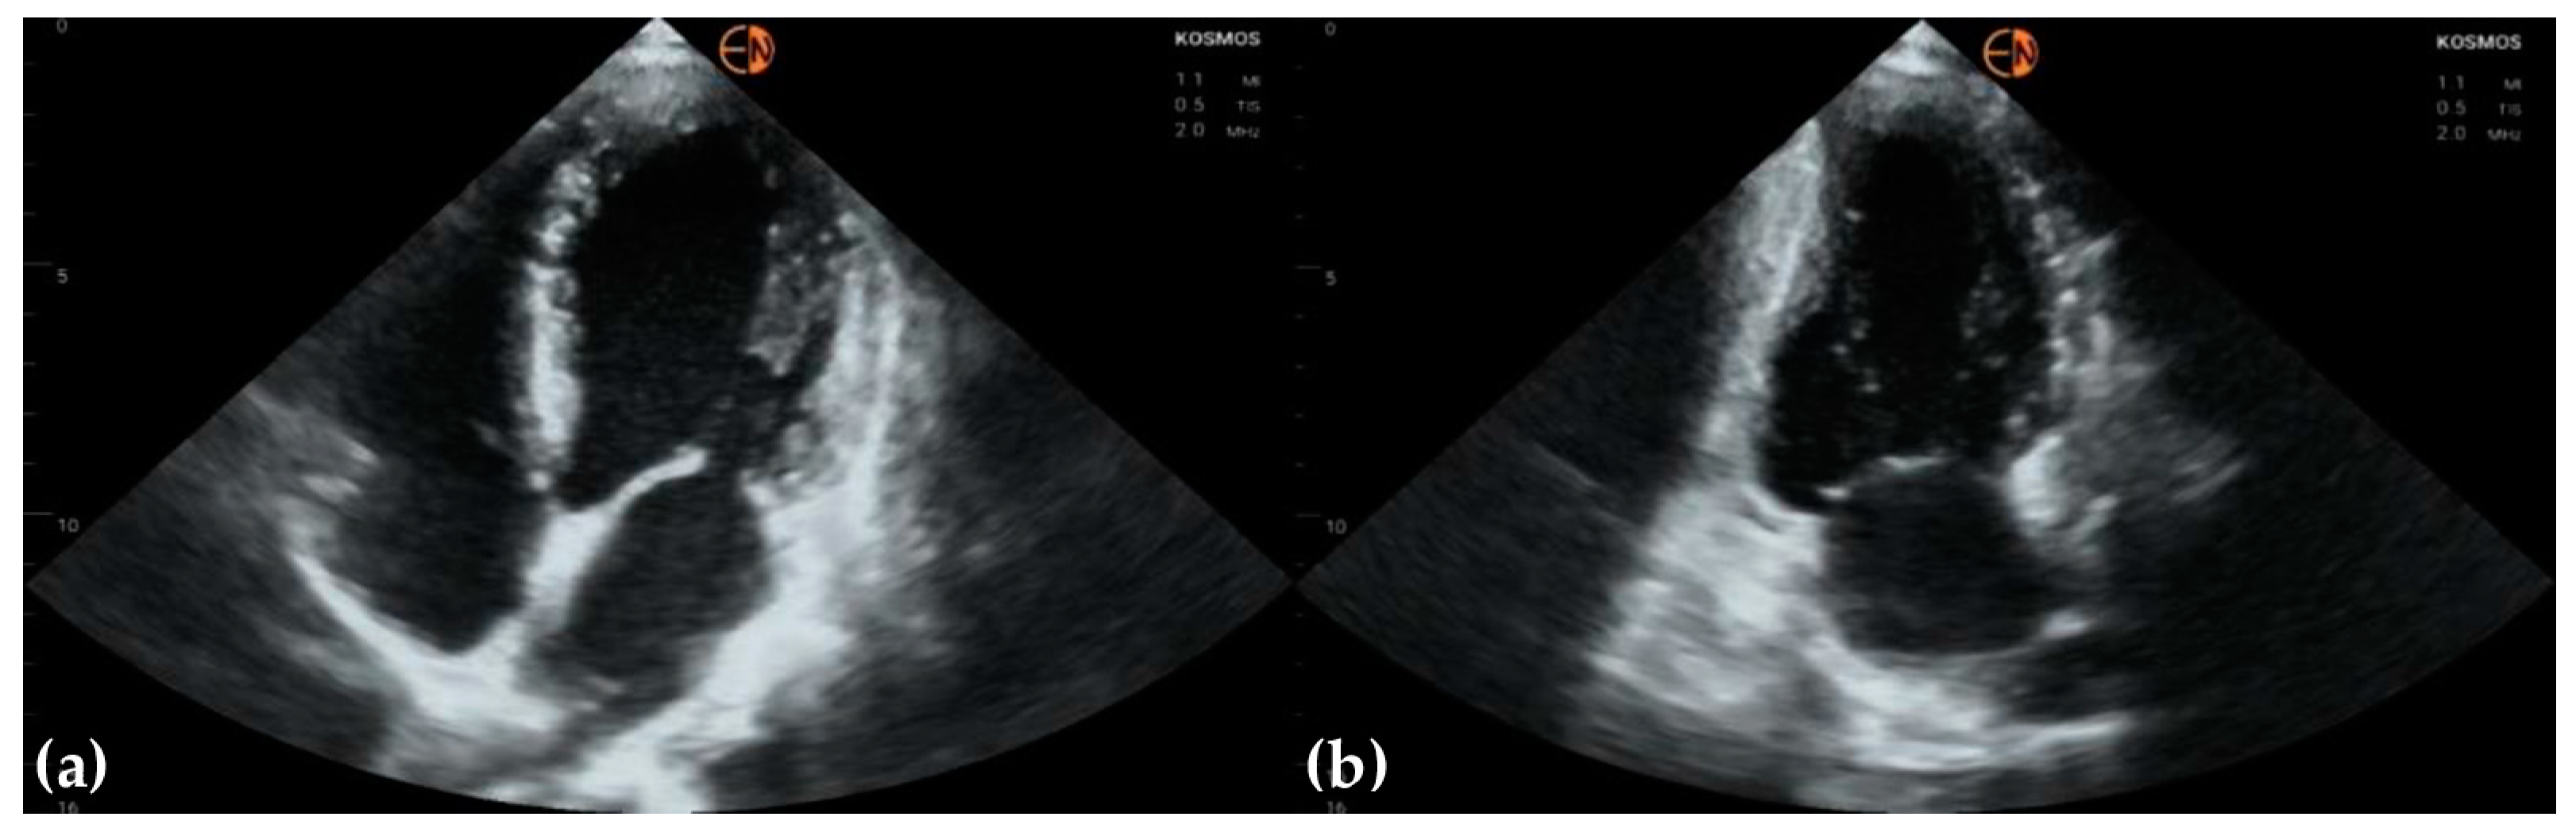

3.3. Valvular Stenosis and Regurgitation

| Aortic valve | 33 (78.6 [62.8 to 89.2]) 0.6557 [0.3862 to 0.9252] | ||

| Mild aortic regurgitation | 10 | 5 | |

| Moderate aortic regurgitation | 1 | 0 | |

| Mild aortic stenosis | 1 | 1 | |

| Severe aortic stenosis | 1 | 1 | |

| Normal | 29 | 35 | |